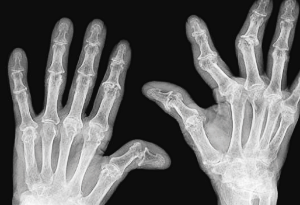

3. 관절 부음

류마티스 관절염은 주로 양쪽의 대칭적인 작은 관절을 표적으로 합니다. 손가락, 발가락의 관절, 손목, 발목, 팔꿈치, 무릎 등이 부어오르고 아프며 따끔거립니다. 이런 부음은 염증으로 인해 관절 주변의 활막이 팽창하고 관절액이 증가하기 때문입니다.

관절에 염증이 생기면 손과 발의 관절 부근 피부가 붉게 변하며, 이는 루마티스 관절염 초기 증상을 시각적으로 확인하는 방법 중 하나입니다.